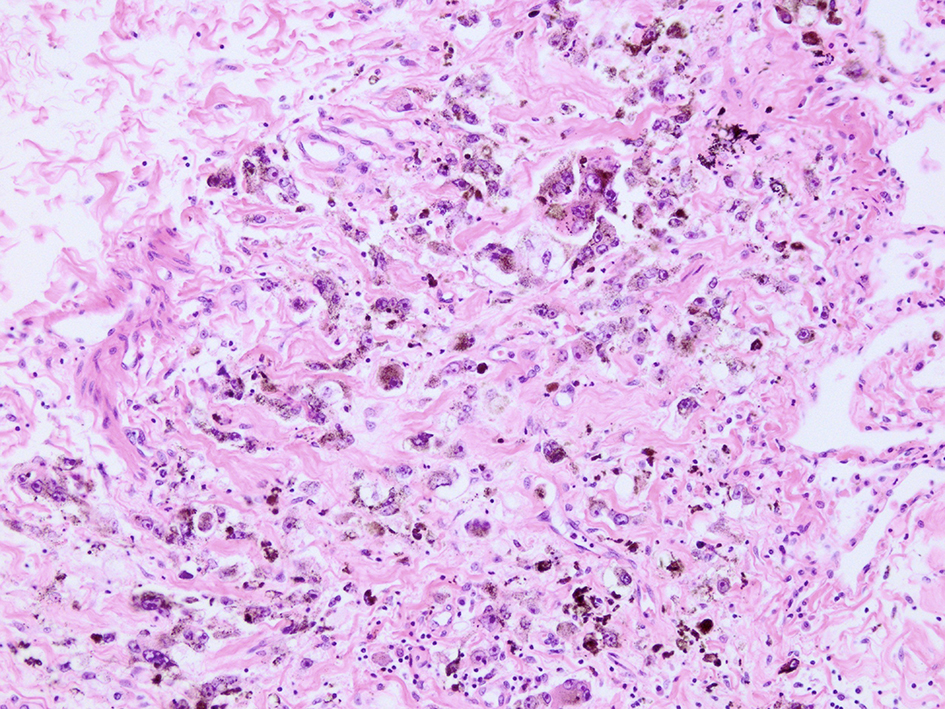

The needle biopsy of left lung tumor performed 36 h before the patient’s death revealed a diffuse invasion of melanocytes without massive necrosis. Immunohistochemical analysis showed positively stained tumor cells by S100, HMB45 and MART1. The Ki-67 staining rate was 30%. The molecular biological examination revealed a positive BRAF V600E mutation.

Microscopic examination of these organs revealed several interesting findings. Massive necrosis of normal hepatocytes and melanoma cells was observed in the liver. The lesion was composed of two parts: 1) centrilobular necrosis without bleeding; and 2) perilobular necrosis with hemorrhage (Fig. 7). Extensive necrosis was observed within the largest pulmonary tumor (Fig. 8), unlike the biopsied specimen taken antemortem (Fig. 9).

![]() Click for large image | Figure 9. Microscopic view of lung lesion on biopsy. Lung metastasis without necrosis was shown. |

The results of the microscopic examination of the lung-biopsied specimen performed antemortem and the autopsied organ clearly present the details. Pulmonary tumor necrosis, which is shown in the autopsied specimen, was not evident in the biopsy. In the autopsied liver specimen, necrosis comprised two areas, including acute and subacute changes.